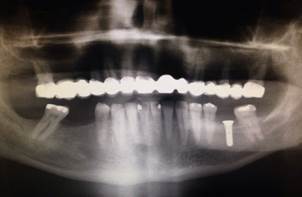

Para la colocación de implantes en sector inferior, con el fin de reemplazar los órganos dentarios 36, 45 y 46, se inició realizando un TAC (tomografía axial computarizada), para evaluar el espesor y densidad ósea; el examen arrojó que existía un buen soporte de hueso para los implantes. Antes de la cirugía se realizó interconsulta con el médico tratante de la patología de base y se suspendió el clopidrogel 75 mg cuatro días antes y se mantuvo el Adiro 100 mg. El procedimiento se inició en la hemiarcada inferior izquierda para reemplazar órgano dentario 36, colocándose anestesia local (mepivacaina® al 3% sin vasoconstrictor), se realizó incisión supracrestal e intrasulcular con bisturí convencional (Bard Parker® N°3, hoja N° 15) para colocar implante STRAUMAN stándar plus de 4,1mm x 10mm de longitud roxolid SLActive; con ayuda de una guía quirúrgica, se inició la perforación con fresa de diamante redonda de 2,3 mm, luego con fresa piloto de 1,2 mm, luego se utilizó la fresa helicoidal 3,5 mm y por último la fresa de perfil, todas a 10 mm de longitud. No se presentó abundante sangrado durante el procedimiento. Se colocó sutura de dos puntos simples nylon negro monofilamento 4/0 (Ethilon™) no reabsorbibles, la cual se retiró a la semana sin complicaciones (Figura 4).

En el postoperatorio se formuló amoxicilina cápsulas de 1g cada 12 horas durante 7 días, y en caso de dolor paracetamol tabletas de 500mg cada 6 horas. Las recomendaciones y la prescripción farmacológica se dieron por escrito. El paciente volvió a tomar el clopidrogel dos días posteriores a la cirugía. Se realizó control a las dos semanas presentando correcta cicatrización y buen resultado funcional y estético de todo el tratamiento (Figura 5).